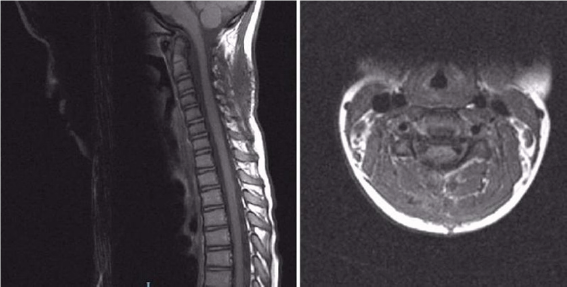

Figure 2: Postoperative MRI scan.

A 6-year old girl was admitted to Pediatric Neurosurgical Unit presenting with severe neck pain, stiffness and decrease in neck movement. She did not have any weakness in upper or lower limbs. Her symptoms started ten days earlier when she received a punch in the neck while she was playing with other children in her kindergarten. Her mother took her to the chiropractic but the symptoms sustained. After the hospitalization hematological profile was analysed and the results were within normal limits (platelet count 333x109/L, prothrombin time 0.73, international normalized ratio 1.15, partial thromboplastin time 29 seconds, fibrinogen 2.1g/L). The MRI scan of the cervical spine showed epidural hematoma with spinal cord compression extending from C2 to C4 vertebral levels (Figure 1). Emergency operation was indicated. Surgery was performed in prone position. Midline vertical skin incision extending from C2 to C5 levels was made and right-sided C4 hemilaminectomy and evacuation of the underlying epidural hematoma were performed. No masses or vascular anomalies were detected during the operation. Skin was suttured and the patient was postoperatively transferred to the Pediatric Neurosurgical Unit. Histopathological diagnosis was: hematoma. She was released from the hospital on the fifth postoperative day. At the moment of the release she was neurologically intact with recuperated neck movement and no neck pain. The MRI scan that was performed 8 weeks after the surgery demonstrated normal postoperative findings with good morphology of the spinal canal and its structures and without signs of the residual epidural collection (Figure 2). During the follow up in the outpatient clinic she was asymptomatic and neurologically intact.